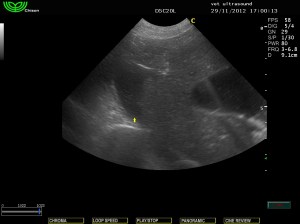

Μικρή παρουσία ασκιτικού υγρού

(πιθανόν λόγω της απώλειας πρωτεινών)